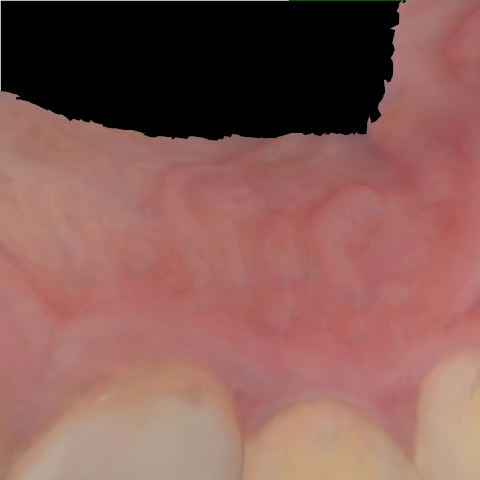

NHD39990

Annotated as "Good"